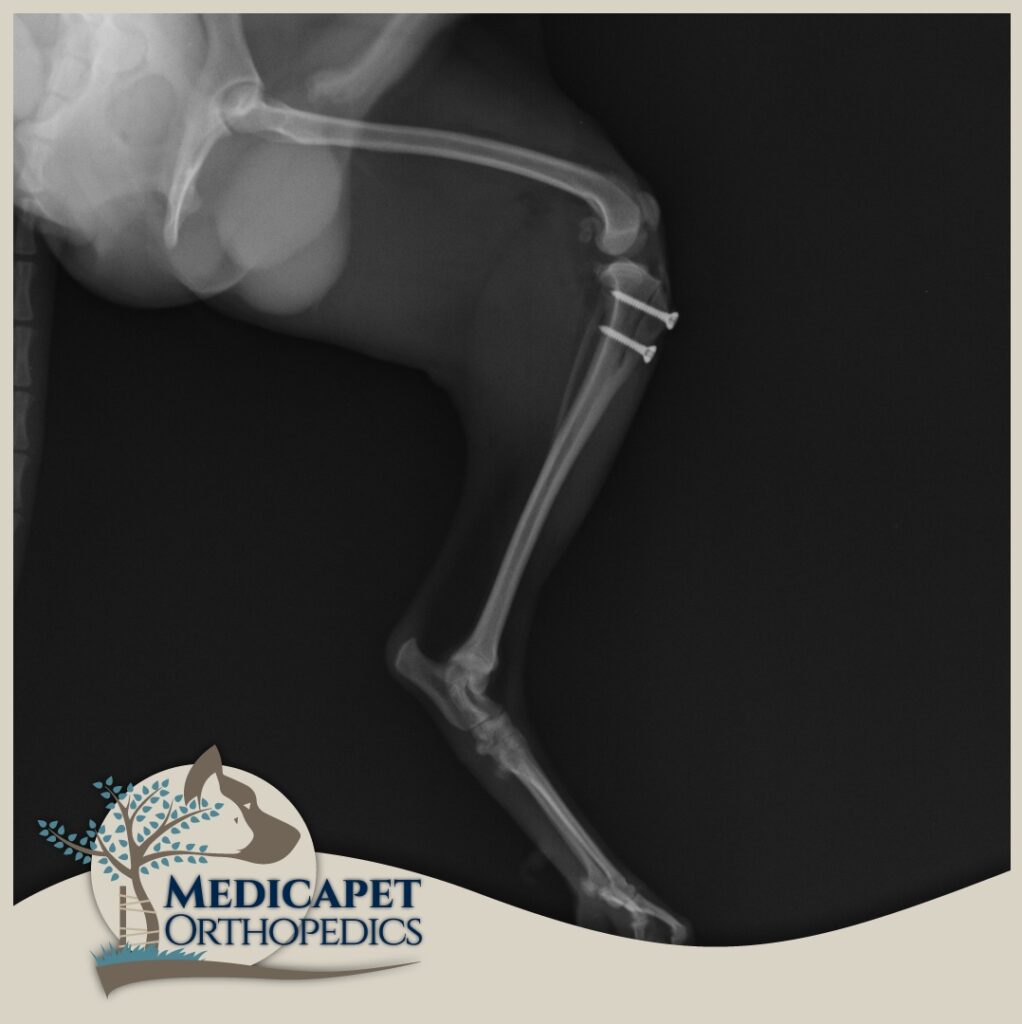

Kaval ve uyluk kemiklerinde ileri derecede eğrilik olan köpeklerin bu kemiklerinin aynı doğrultuya getirilmesini amaçlayan ve düzeltme osteotomileri ile bu kemiklerin doğru pozisyonda yeniden şekillendirildiği işlemlerdir. Daha çok ileri derecede deformasyon olan olgularda uygulanır. Yeniden şekillendirilen uzun kemikler son hallerinde iyileşebilmeleri için plak ve vidalarla sabitlenirler.